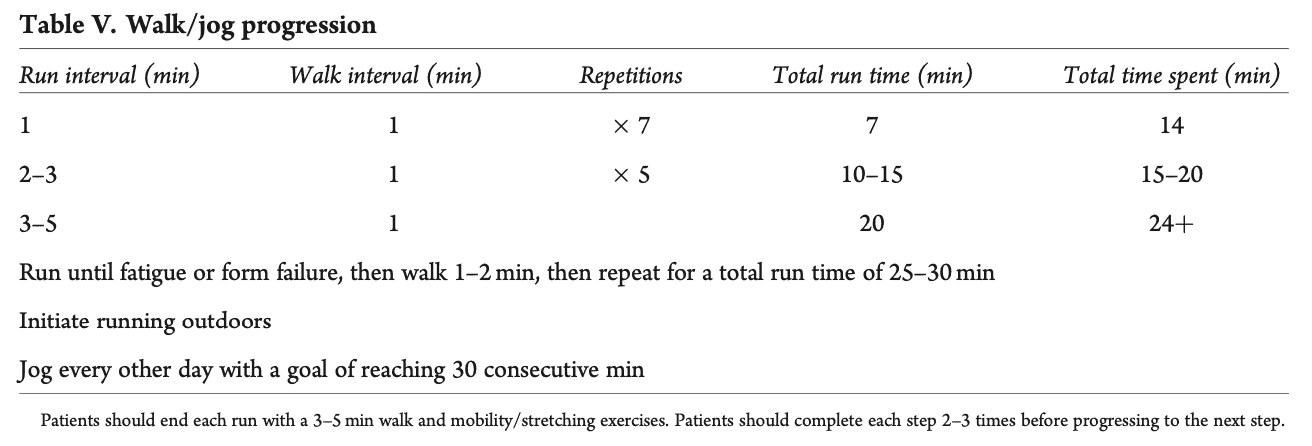

- 该计划的第一阶段是步行计划,从跑步机上开始,逐渐发展到户外活动。 要求是能够以大约每小时 3.5 英里(相当于每小时 5.6 公里)的速度步行 30 分钟。

如果参与者成功完成了第一阶段和第二阶段的 I 级负重训练,行走时不会一瘸一拐,并且在日常活动中没有疼痛感,就可以进入步行/跑步计划。 这里的建议也是在跑步机上启动该计划。 必须遵守以下规则(i)不爬山或上坡,(ii)不做速度练习,(iii)练习姿势,(iv)每隔一天跑一次。 理想情况下,他们应继续进行二级和三级负重训练。